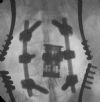

Anterior Corpectomy and vertebral replacement for acute root compression following burst fracture L2